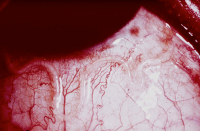

Las filarias adultas forman nódulos fibrosos en los tejidos subcutáneos, fundamentalmente en la cabeza y los hombros, o en la cintura pelviana y las extremidades inferiores. La filaria hembra expulsa microfilarias que emigran a través de la piel. Estas microfilarias al morir causan una erupción muy pruriginosa, que evoluciona a una dermatitis crónica con alteración de la pigmentación (“piel de leopardo”), edema y atrofia de piel. A menudo las microfilarias llegan a los ojos, donde su invasión y muerte posterior produce alteraciones visuales y ceguera.

El diagnóstico de laboratorio se hace por demostración del gusano adulto en los nódulos extirpados o por demostración de las microfilarias en biopsias de piel.